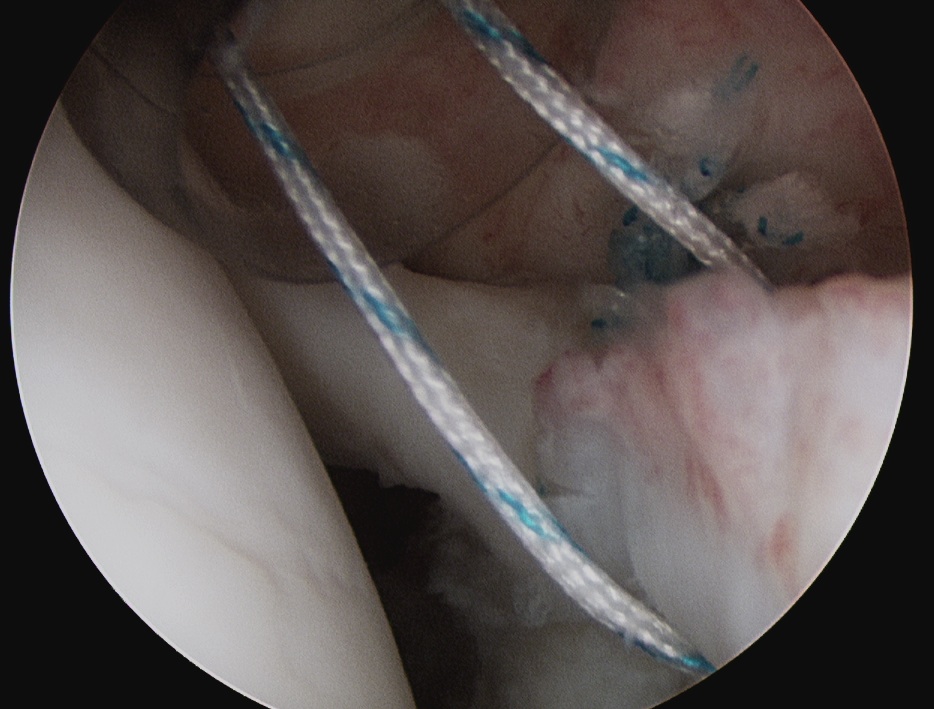

3. Anchors

Usually 3 anchors is a minimum

- suture through each cannula

- limb through W portal will be the suture limb that is passed

- best to pass the suture passer above the biceps to get good bite

- retrieve sutures and tie from port of Wilmington

Posterior 2 anchors